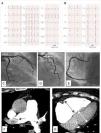

Una mujer de 78 años de edad hipertensa y obesa acudió al servicio de urgencias por presentar dolor torácico opresivo e intermitente de 2 días de evolución. El electrocardiograma (ECG) mostró una elevación del segmento ST en las derivaciones torácicas inferiores y derechas, indicativa de un infarto de miocardio inferior con afectación del ventrículo derecho (VD) (fig. 1A). El ECG previo era normal (fig. 1B). La paciente se sometió a un cateterismo de urgencia, que no constató ninguna oclusión coronaria (figs. C, D y E). Debido a que también presentaba disnea e hipoxemia, se solicitó una prueba del dímero D, cuyo resultado fue elevado, alrededor de 24.000pg/dl. La angiografía pulmonar confirmó la sospecha diagnóstica de embolismo pulmonar (EP) agudo (fig. 1F) con dilatación del VD (fig. 1G). Se inició tratamiento con heparina no fraccionada, con la consiguiente mejoría de la sintomatología.

A) Electrocardiograma de 12 derivaciones en fibrilación auricular, que muestra una elevación del segmento ST en las derivaciones III, AVF, AVR y V1, y depresión del segmento ST en las derivaciones I y AVL, que señala un infarto de miocardio inferior. También se observa una elevación del segmento ST en las derivaciones precordiales torácicas V4R, V5R y V6R, que demuestra la afectación del ventrículo derecho. B) Electrocardiograma de 12 derivaciones obtenido algunos meses antes: en ritmo sinusal y sin alteraciones del segmento ST. C) Angiografía coronaria que no muestra lesiones en la arteria coronaria circunfleja (LCX), D) en el tronco coronario izquierdo (LMCA), en la arteria coronaria descendente anterior (LAD), ni E) en la arteria coronaria derecha (RCA). F) AngioTC pulmonar que revela un embolismo pulmonar bilateral (flechas) con G) dilatación de ventrículo derecho (flechas).